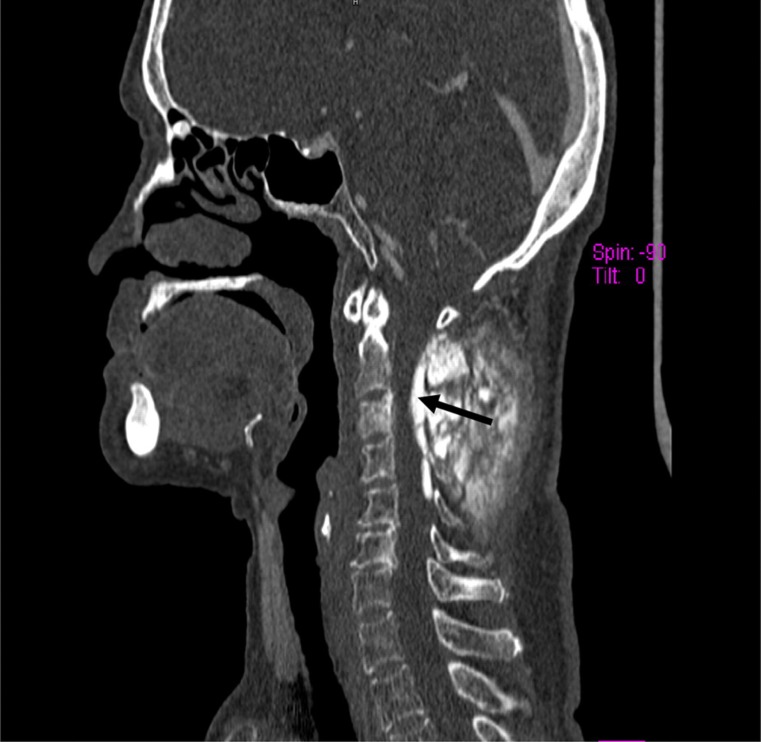

我们报告一个非常罕见的病例高级别骨肉瘤的颈椎在62岁的妇女。她表现出相对较短的后颈部肿胀和颈部淋巴结病病史。这与最初的声音嘶哑、体重明显减轻和右上臂神经根症状相关,并发展为截瘫。根据颈部的MR和CT成像以及右侧锁骨上肿大淋巴结的切除活检,组织学显示为颈椎高级别原发性骨肉瘤。

We report a very rare case of a high grade osteosarcoma of the cervical spine in a 62-year-old woman. She presented with a relatively short history of a swelling in the posterior neck and cervical lymphadenopathy. This was associated with hoarseness of the voice, significant weight loss, and right upper arm radicular symptoms initially, progressing to paraplegia. Based on MR and CT imaging of the neck and an excision biopsy of an enlarged right supraclavicular lymph node, the histology revealed a high grade primary osteosarcoma of the cervical spine.